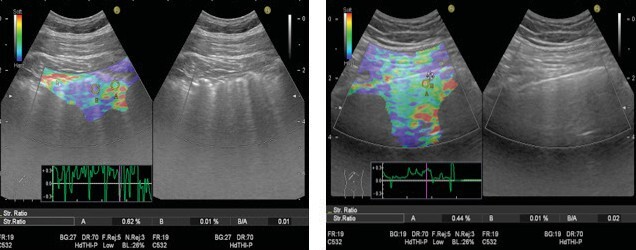

Introduction: Ultrasound elastography (US-E) is a novel, tissue stiffness-sensitive imaging method. We aimed to investigate whether lung ultrasound (US) and US-E can play a role in diagnosing interstitial lung diseases (ILDs) in which lung elasticity is affected due to fibrosis.

Materials and methods: A prospective cohort study. Patients with ILD were defined as ''ILD group'' and with other pulmonary diseases as ''control group". All subjects were examined and compared by lung US in B and elastography modes. Besides, the relationship between ultrasonography and high-resolution computerized tomography (HRCT) and chest X-ray findings was evaluated.

Result: A total of 109 patients, 55 in ILD and 54 in the control group, with a mean age of 62 ± 14 years, were included. A positive correlation was found between the Warrick score (calculated from HRCT to determine the severity of ILD) and the number of B-lines (discrete vertical reverberation artifacts, indicating interstitial lung syndrome) in lung US (p= 0.001, r= 0.550) in the ILD group. In US-E, blue color (meaning more rigid tissue) dominated in the ILD group, and green color (indicating medium tissue stiffness) dominated in the control group (p= 0.001). Lung US diagnosed the ILD with 69% accuracy, 80% sensitivity, and 60% specificity compared to HRCT. Combined with chest X-ray, diagnostic accuracy was 74%, sensitivity 60%, and specificity 89%.

Conclusions: Although lung US and US-E are not superior to gold standard HRCT in diagnosing ILDs, they can still be accepted as promising, novel, noninvasive tools, especially when combined with chest X-rays. Their role still needs to be clarified with further studies.